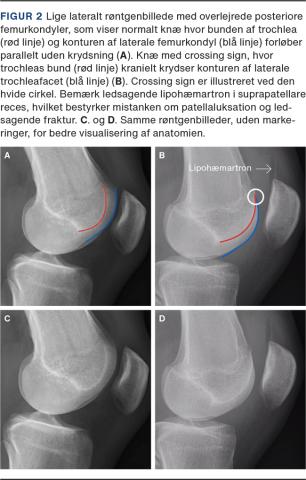

DEFINITIONER

Den vigtigste anatomiske risikofaktor for OPI er TD. Hertil kommer patella alta og forøget TT-TG-afstand. TD inddeles i type A-D [17], som beskriver forskellige typer af flad/konveks trochlea. Patella alta er en tilstand, hvor patella er placeret for højt i forhold til trochlea og først ledes ind i føringsfuren, når knæet er bøjet noget. Forøget TT-TG-afstand beskriver graden af lateralisering af tuberositas tibia ift. centrum af trochlea [2, 3]. Den mest betydende risikofaktor er ifølge Arendt et al TD [4]. Diagnosticering af patella alta og forøget TT-TG-afstand foretages af ortopædkirurger eller muskuloskeletalradiologer. TD kan identificeres på lige laterale røntgenbilleder (sideoptagelser) og har tre kardinaltegn: crossing sign, double contour sign og supratrochlear spur, som alle skal lede tankerne hen på TD (Figur 1). Crossing sign er til stede ved alle fire typer af TD [18] og er derfor den vigtigste anomali at kunne erkende på røntgenoptagelser. Det defineres som en overkrydsning af trochleabunden og den anteriore kant af laterale femurkondyl. Overkrydsningen kan erkendes helt kranielt i trochlea femoris (Figur 2B) [2]. I normale knæ vil disse linjer være tilnærmelsesvis parallelle (Figur 2A).

RØNTGENUNDERSØGELSER

Patienter med tegn på akut tilfælde af OPI skal altid have taget røntgenbilleder ved den initiale kontakt. Røntgenundersøgelse efter en lateral patellaluksation skal indbefatte et anterior-posterior-billede, en lateral optagelse af knæet samt en tangentialoptagelse af patella [1]. Ved disse er det muligt at finde evt. osteokondral fraktur, tegn på TD (crossing sign) samt evt. at vurdere patellas højde (patella alta eller baja). Tangentialoptagelsen tages primært for at udelukke osteokondral fraktur, som kan være vanskelig at erkende på AP- og lateraloptagelse. Tangentialoptagelsen af patellofemoralleddet viser ved rutineoptagelser som oftest ikke den proksimale del af trochlea og har derfor begrænset værdi i diagnosticeringen af TD. For at man kan erkende crossing sign, skal det laterale røntgenbillede tages lige (true lateral), dvs. at de posteriore femurkondyler skal være overlejrede (Figur 2).

Crossing sign er enkelt at erkende, også for uerfarne. Underinddeling af TD på baggrund af double contour sign og supratrochlear spur er mindre væsentlig for den indledende diagnostik. Disse bedømmes af en ortopædkirurg eller en muskuloskeletalradiolog. Ligeledes bedømmes evt. patella alta. Dog kan dette ved kendskab til målemetoden ligeledes udføres i skadestuen, lettest i form af Insall-Salvati Index [23]. Røntgenfund sammenholdt med anamnese og antallet af patellaluksationer bør herefter resultere i en klar plan for udredning og behandling. Det skal afgøres, om patienten skal ses af egen læge til bevægekontrol og evt. henvisning til struktureret træning, henvises til ambulant vurdering eller henvises til subakut operation (Figur 4). Forskellen fra den nuværende behandlingsstrategi ligger i, at fund af crossing sign ved både førstegangspatellaluksation og recidiverende patellaluksation skal udløse henvisning til ortopædkirurgisk vurdering under mistanke om TD.